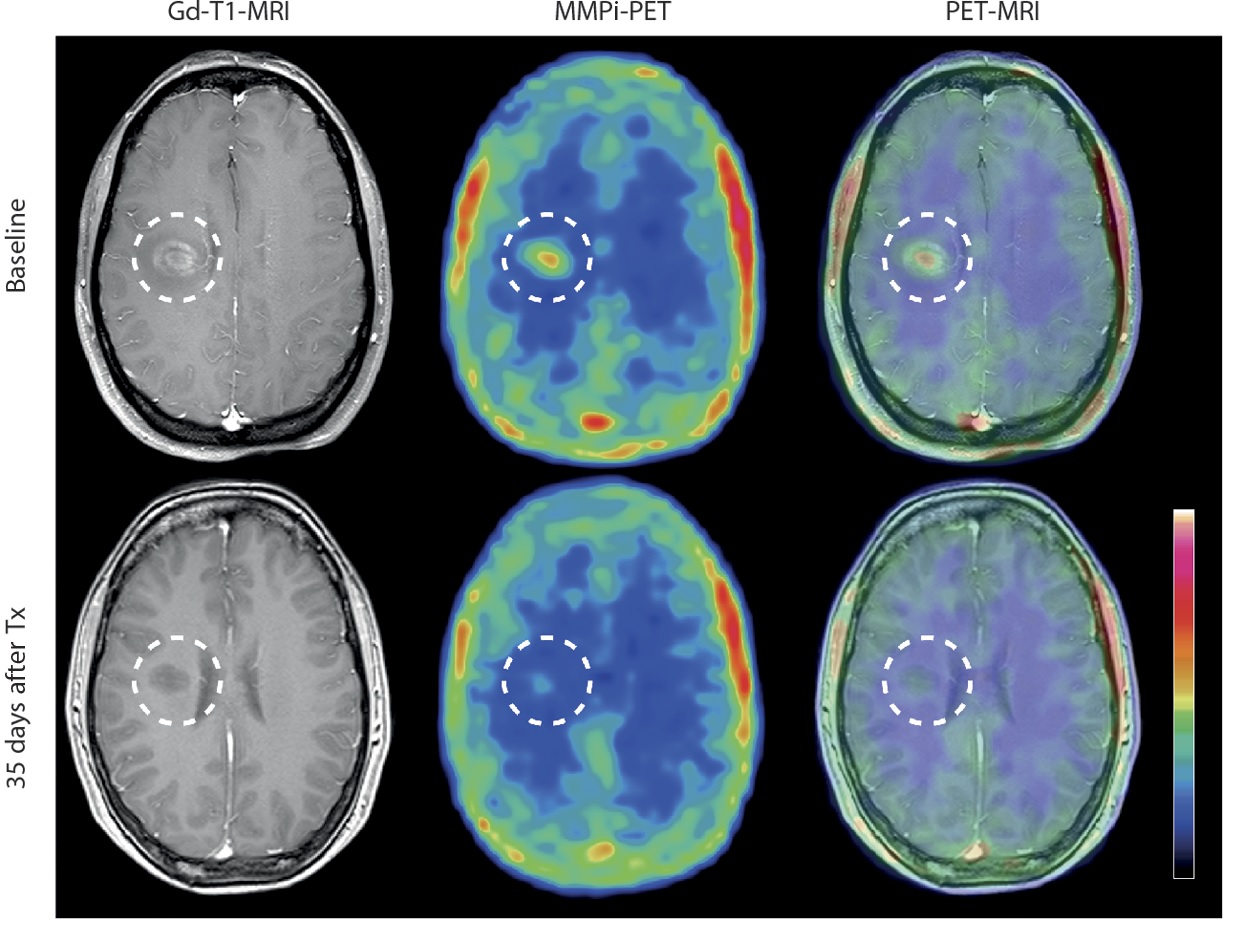

Figure: A Gadolinium-enhanced T1-MRI image is co-registered with an MMPi-PET scan in a patient suffering from an acute attack of relapsing-remitting MS and shows the MMPi tracer is sensitive to the treatment with the corticosteroid methylprednisolone (Tx).

From Gerwien, H. et al. Sci. Transl. Med. 8, 364ra152, (2016). Reprinted with permission from AAAS.

In patients, T1-gadolinium-enhanced magnetic resonance imaging (T1-Gd MRI) is able to resolve lesions; however this imaging modality cannot distinguish which lesions are newer and have an on-going infiltration process and is, therefore, ineffective at measuring lesion age. In humans, the radiolabelled tracer 18F-MMPi was detected using positron emission tomography (PET) and shown to distinguish between lesions with ongoing leukocyte infiltration, lesions with post-inflammatory BBB dysfunction (where leukocytes are no longer present) and patients receiving anti-inflammatory treatment. Because one of the main features in the diagnosis of MS relies on the ability to detect the gradual appearance of lesions in the brain and the CNS, it follows that the ability to detect one of the critical events associated with BBB rupture and its associated localized inflammation may have significant impact in the way these diseases are managed and treated.